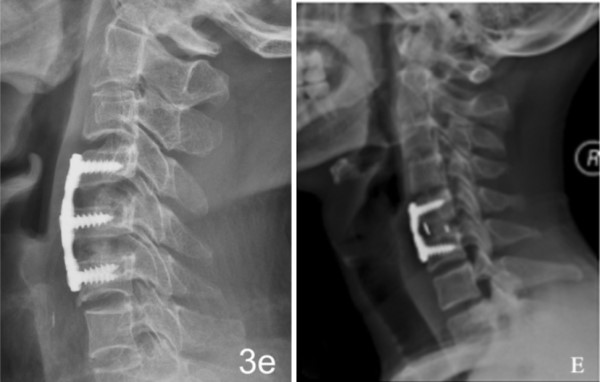

注册证名称:医用纳米羟基磷灰石/聚酰胺66复合骨充填材料

注册证号:国械注准20183131720

1.优异的生物相容性和生物活性

2.力学性能与自体骨匹配

3.弹性模量接近自体骨,有效减少应力遮挡